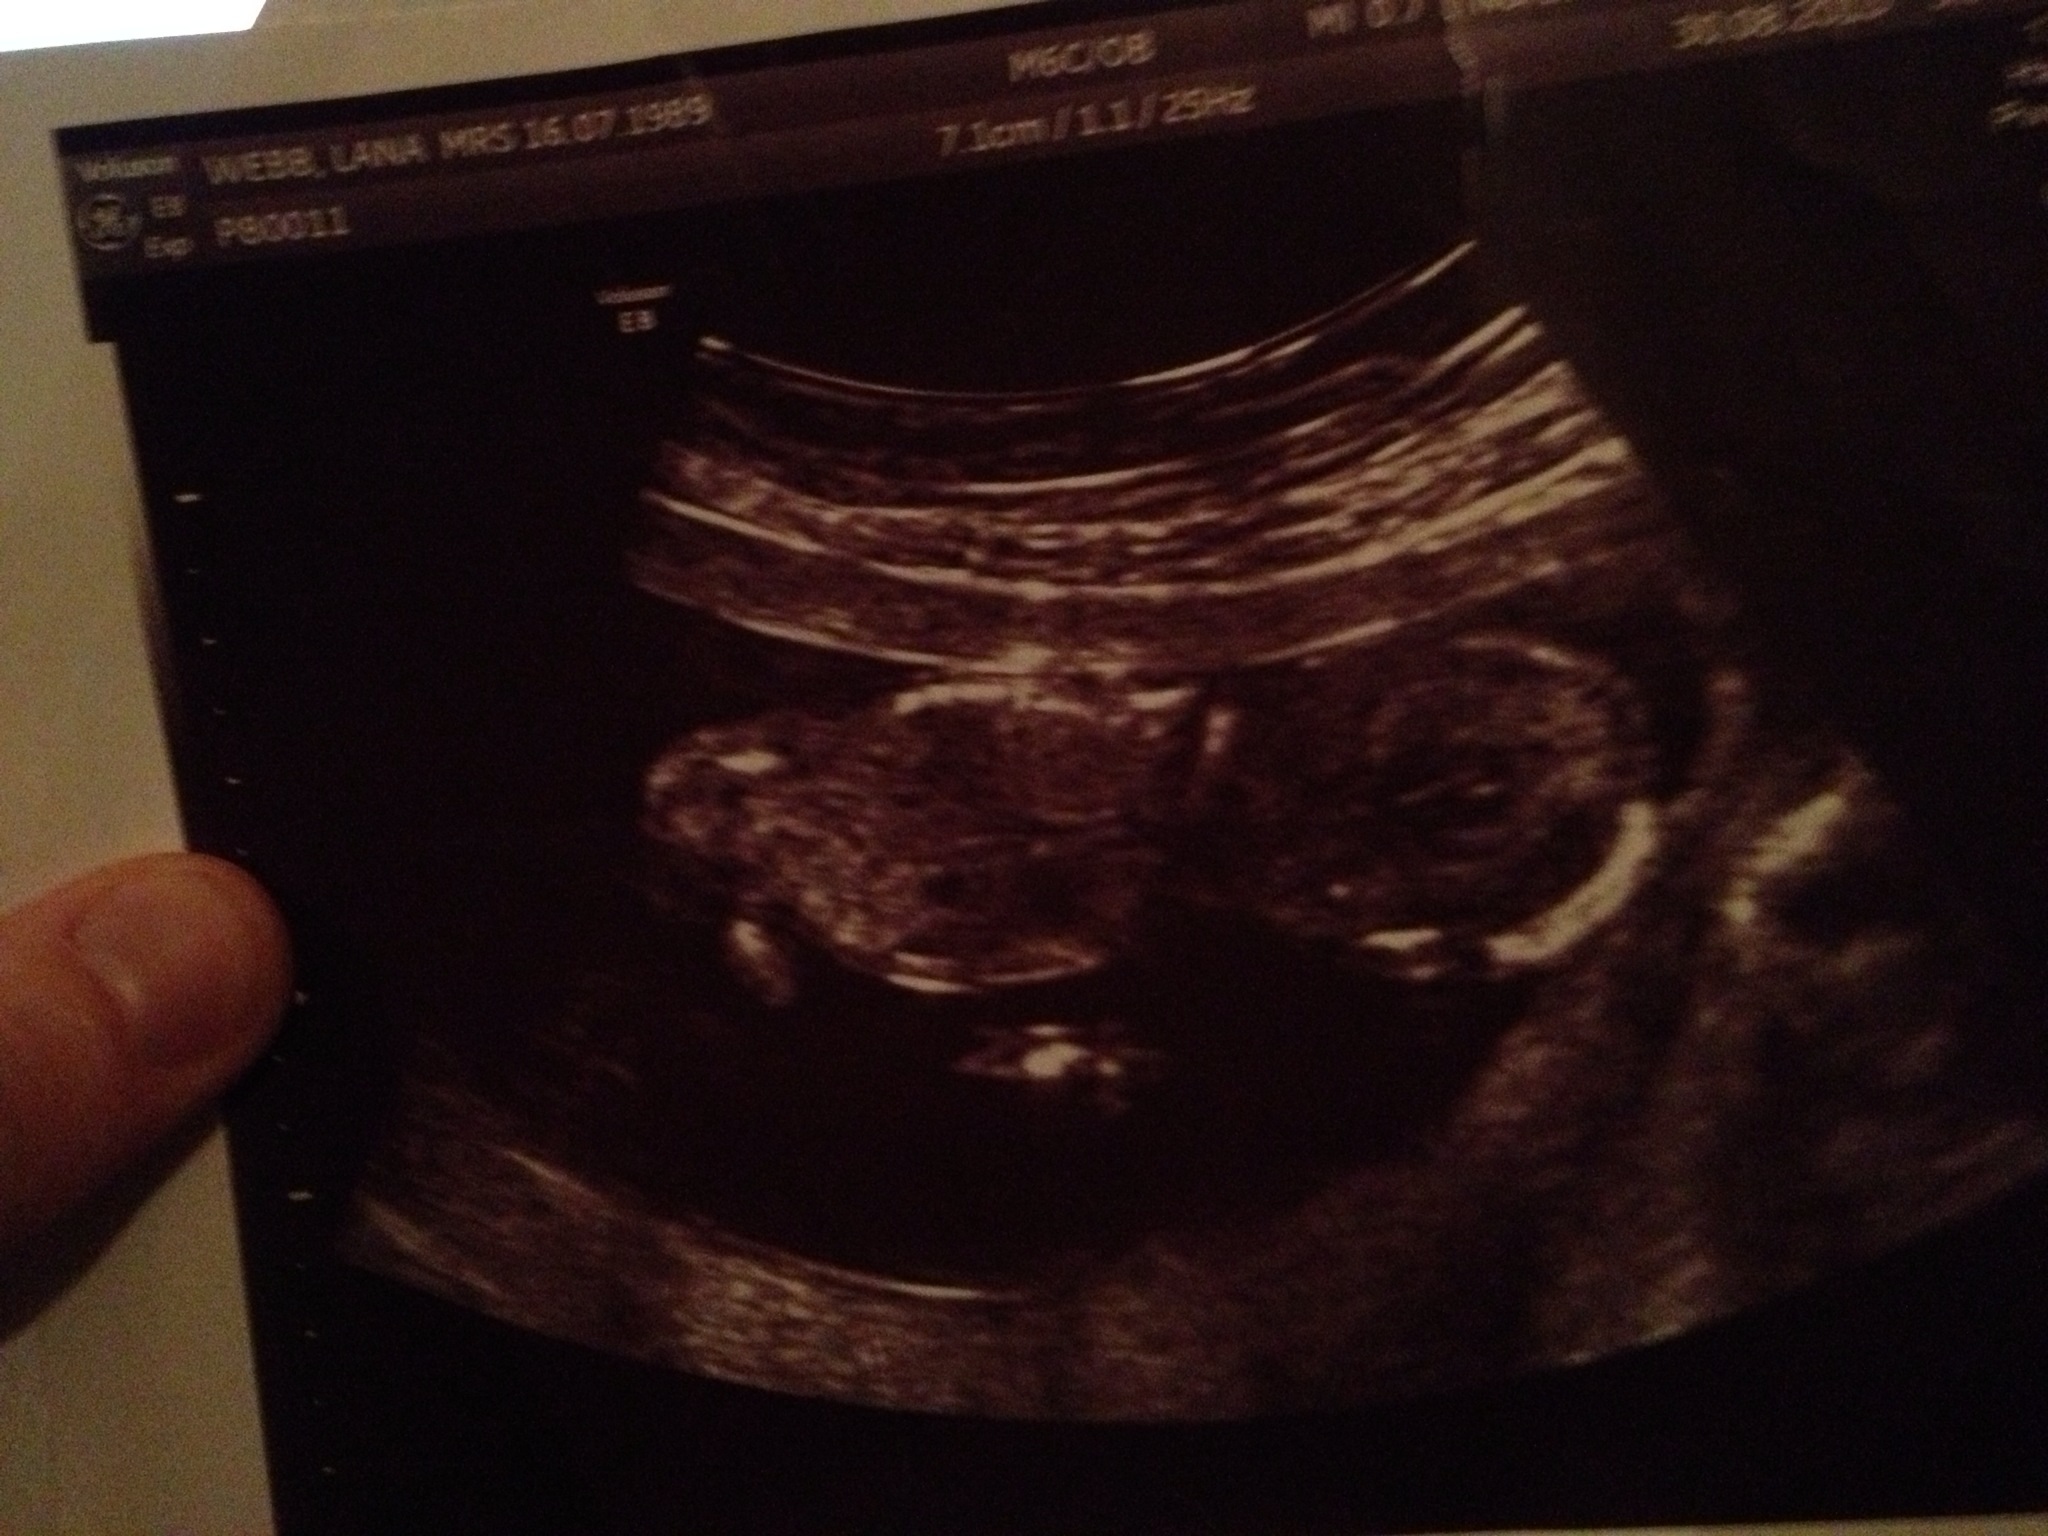

Is my baby a boy or girl?